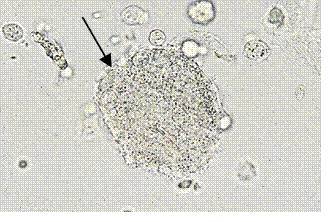

10、箭头所指细胞内结构的名称:脂肪颗粒细胞

12、箭头所指细胞内结构的名称:脂肪颗粒细胞 复粒细胞